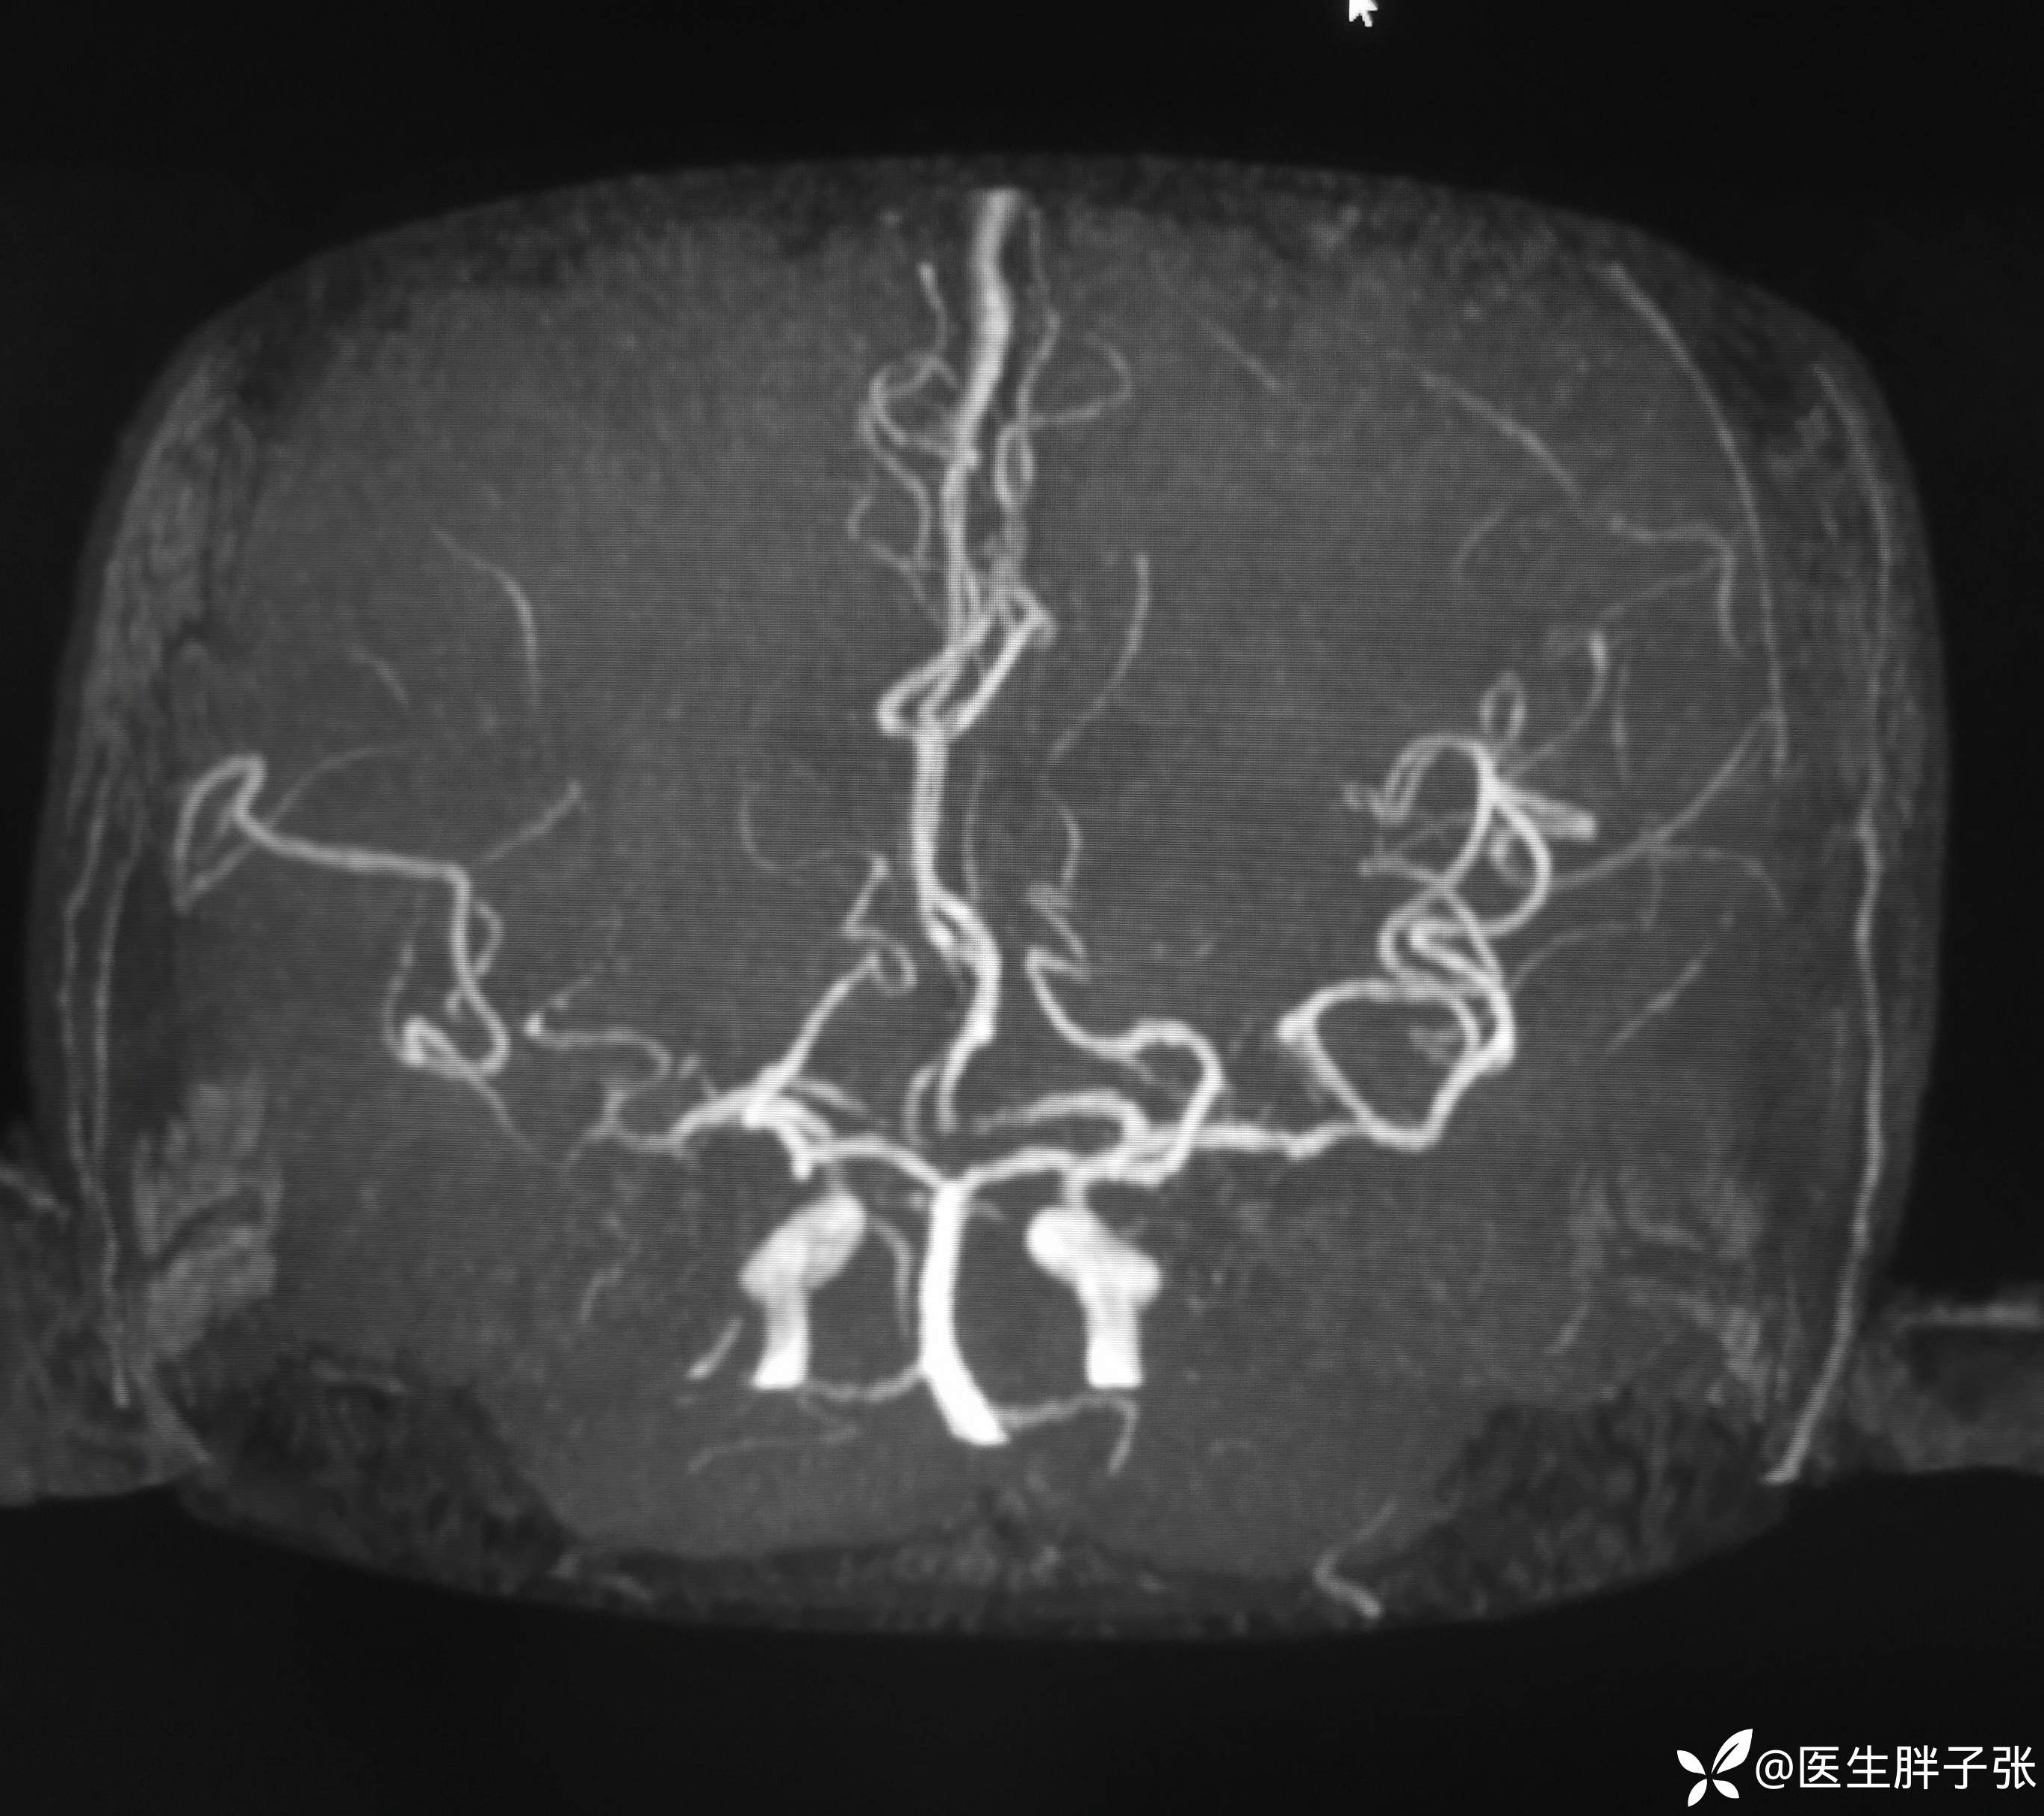

颅脑MR:右侧颞叶新近梗死灶;老年性脑改变;右侧大脑中动脉部分M2段及以远未见显示,建议头颈部CTA检查。

溶栓过程顺利,无并发症。患者发病前有腹泻,MRA提示右侧大脑中M2闭塞可能